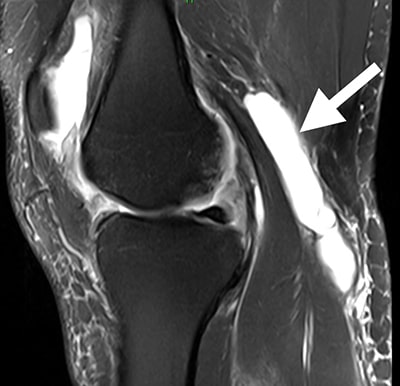

Esta RM muestra un área llena de líquido detrás de la rodilla, la ubicación característica del quiste de Baker.